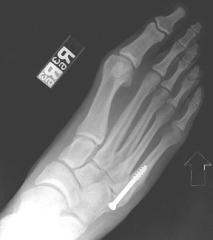

While lay people do not require surgery for a Jones fracture the demands of NFL play require that surgery be performed on the foot when injury first occurs. The surgery known as an “intramedullary fixation” involves the insertion of a nail long ways into the middle of the bone to help support the area during movement.